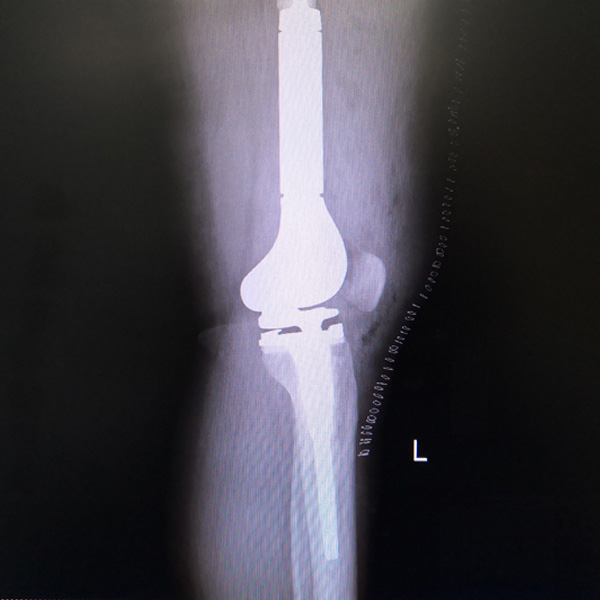

• 膝關節內翻膝關節內翻手術后手術前

膝關節內翻

患者劉某某,女66歲,左側膝關節嚴重內翻(俗稱的“羅圈腿”),疼痛到不能生活自理。經平臺推薦到哈爾濱醫科大學附屬第二醫院骨關節科就診,......

在線咨詢+更多詳情+